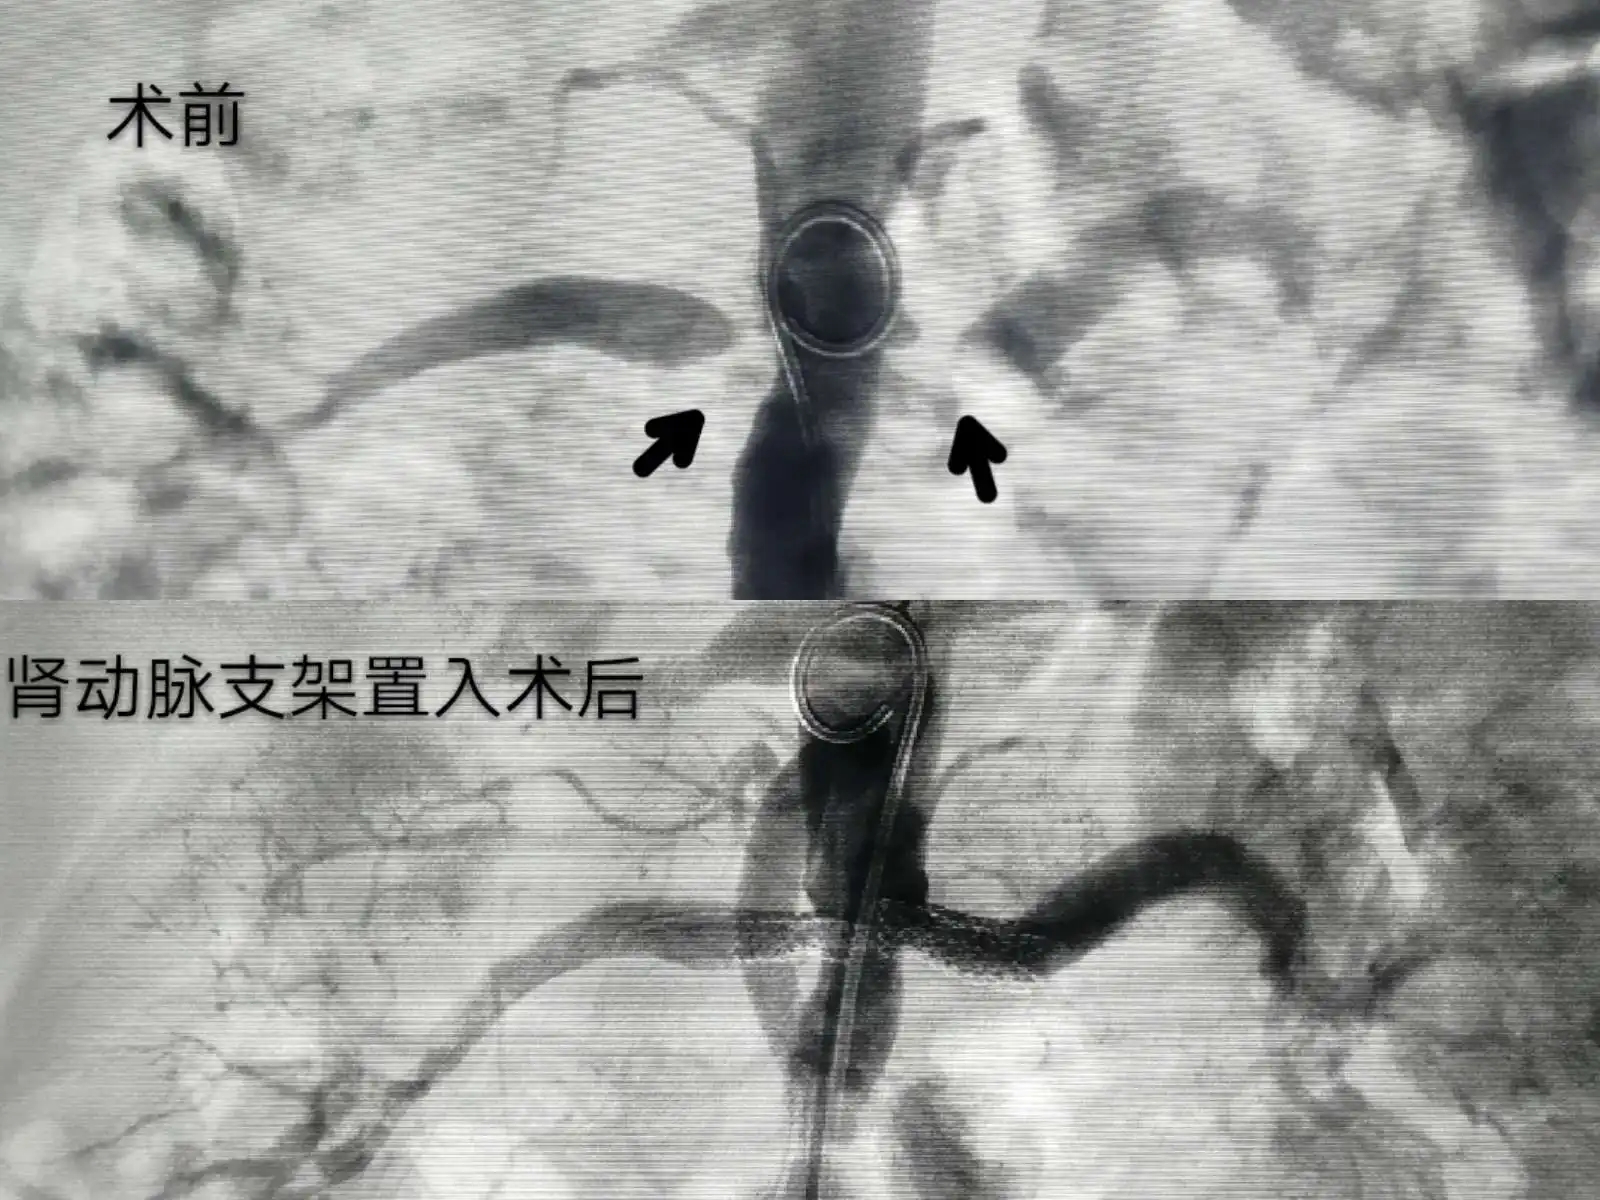

药物球囊最早是用于冠脉的治疗,现在下肢动脉领域也有应用,因为球囊最终是要撤出人体的,所以该技术是没有在人体内植入外界材料的,也就有不少人认为该技术比支架介入要好,那么真的是这样的吗?其实药物球囊目前也有其局限,难以完全取代支架手术。

首先就是价格问题,集中采集之后支架的价格大幅下降,但目前药物球囊并没有集中采集,其单价大概在一万五左右;再者金属支架对于血管狭窄处有支撑的作用,而药物球囊则无此功能;所以药物球囊是有其适用的患者人群的。